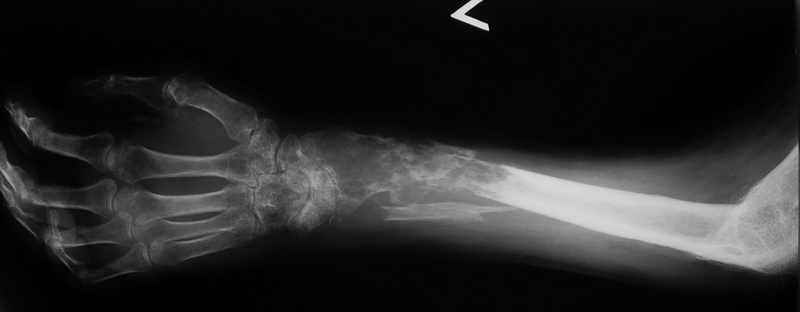

Всем привет!Кому интересно - может лицезреть мое личное наблюдение первичной костной лимфомы с поражением правой большеберцовой кости (см. аттач). Пациент: мужчина, 46 лет. Анамнез прослеживается в течение 1,5 лет - начало заболевания с появления болей.С уважением, Виталий Тазалов.

Извините, но впечатление какое-то агрессивное! Вот Вам моя лимфома!

И продолжение - Вам под стать: а вот моя!